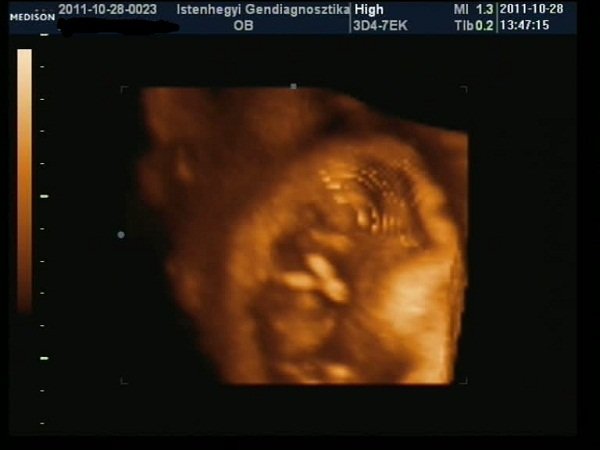

Nagyon jó volt az Istenhegyin, pikk-pakk levették a vért, aztán nem egészen egy óra múlva megvolt az uh, rettenetesen alapos volt a doki, 6-szor is megmérte a tarkóredőt (mert a határ határán volt, 2.4, és 2.5 felett szokott rezegni a léc, 3 felett rossz), aztán jól megnéztük mindenét, még 4D-ben is (sose voltam ilyenen:D), mindent elmagyarázott, végül kaptam egy dvd-t, és jó véreredményt kívánt.

Hoztam néhány képet a kukiról és az x-faktorról (utóbbit megoldókulccsal:D), valamint a "nagyokról", ahogy birtokba veszik a kanapét, és a lehető legszínesebben próbálják funkcióra bírni, valamint az Angelina Jolie Klub-ról, amit különböző balesetekben szerzett sebesüléseik miatt nyitottam…